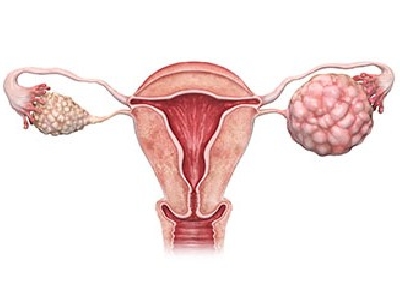

Gynaecologic Oncology

Gynaecologic Oncology

Gynaecologic Oncology

Gynaecologic Oncology